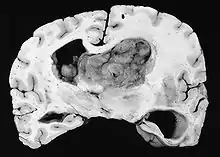

Generalmente, el SEGA se muestra como una lesión nodular bien circunscrita en relación con la masa cerebral adyacente. En la literatura son muy raros los casos de propagación (por ejemplo, a la médula espinal) y de malignización.[2] Este tumor es claramente visible en la resonancia magnética, donde presenta realce tras la aplicación del medio de contraste.

Histológicamente, son características de la lesión las células gigantes astrocíticas; sin embargo, la morfología de las células tumorales puede variar desde células poligonales con citoplasma vítreo y núcleos ganglioides hasta células fusiformes en una matriz fibrilar. Las células tumorales muestran una expresión variable de GFAP, S-100, sinaptofisina y neurofilamentos.